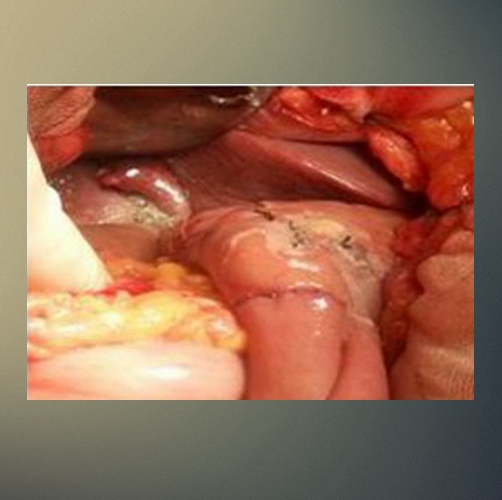

肝門區膽管癌

肝門膽管癌晚期